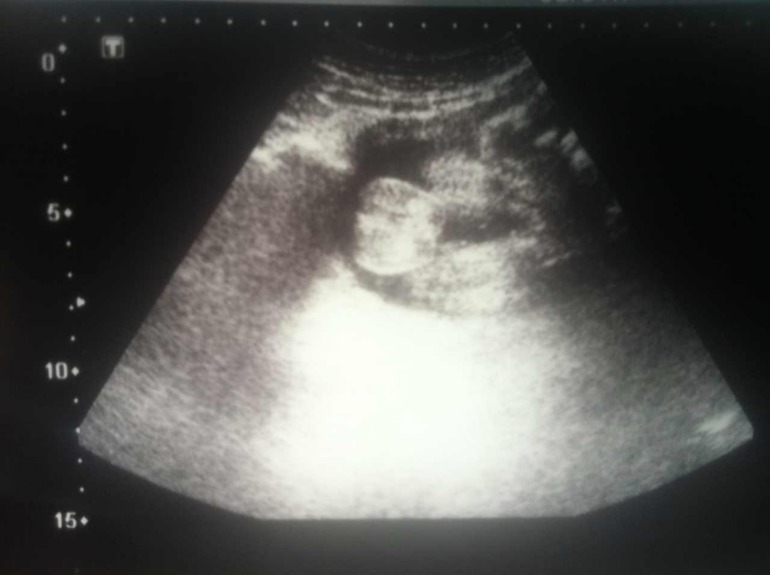

Вот этот симпотичный персик посередине

- это мошоночка!!! Чтобы папа не переживал, узисты не ошиблись, ждем сынульчика =))))))))))